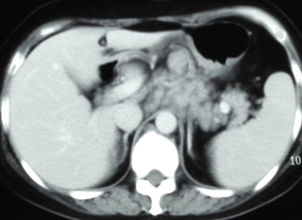

腹部CT:肝胃韧带、肝十二指肠韧带、门腔间隙、胰腺周围、腹主动脉周围多发大小不等的软组织结节影,部分融合成团。

治疗2周期、4周期后肿瘤标志物及CT变化情况如下:

腹膜后淋巴结治疗3月(4周期)